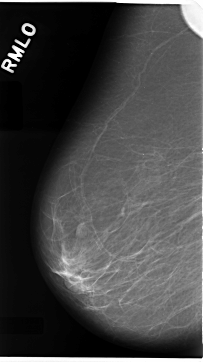

C_0079_1.RIGHT_MLO

RIGHT_CC LINES 4680 PIXELS_PER_LINE 2768 BITS_PER_PIXEL 12 RESOLUTION 50 NON_OVERLAY

RIGHT_MLO LINES 4696 PIXELS_PER_LINE 2632 BITS_PER_PIXEL 12 RESOLUTION 50 NON_OVERLAY